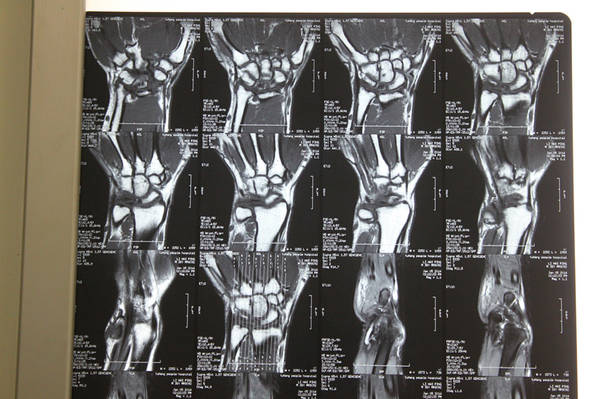

[手部疾病] 月骨缺血性坏死

患者  36岁  无外伤性腕关节疼痛,